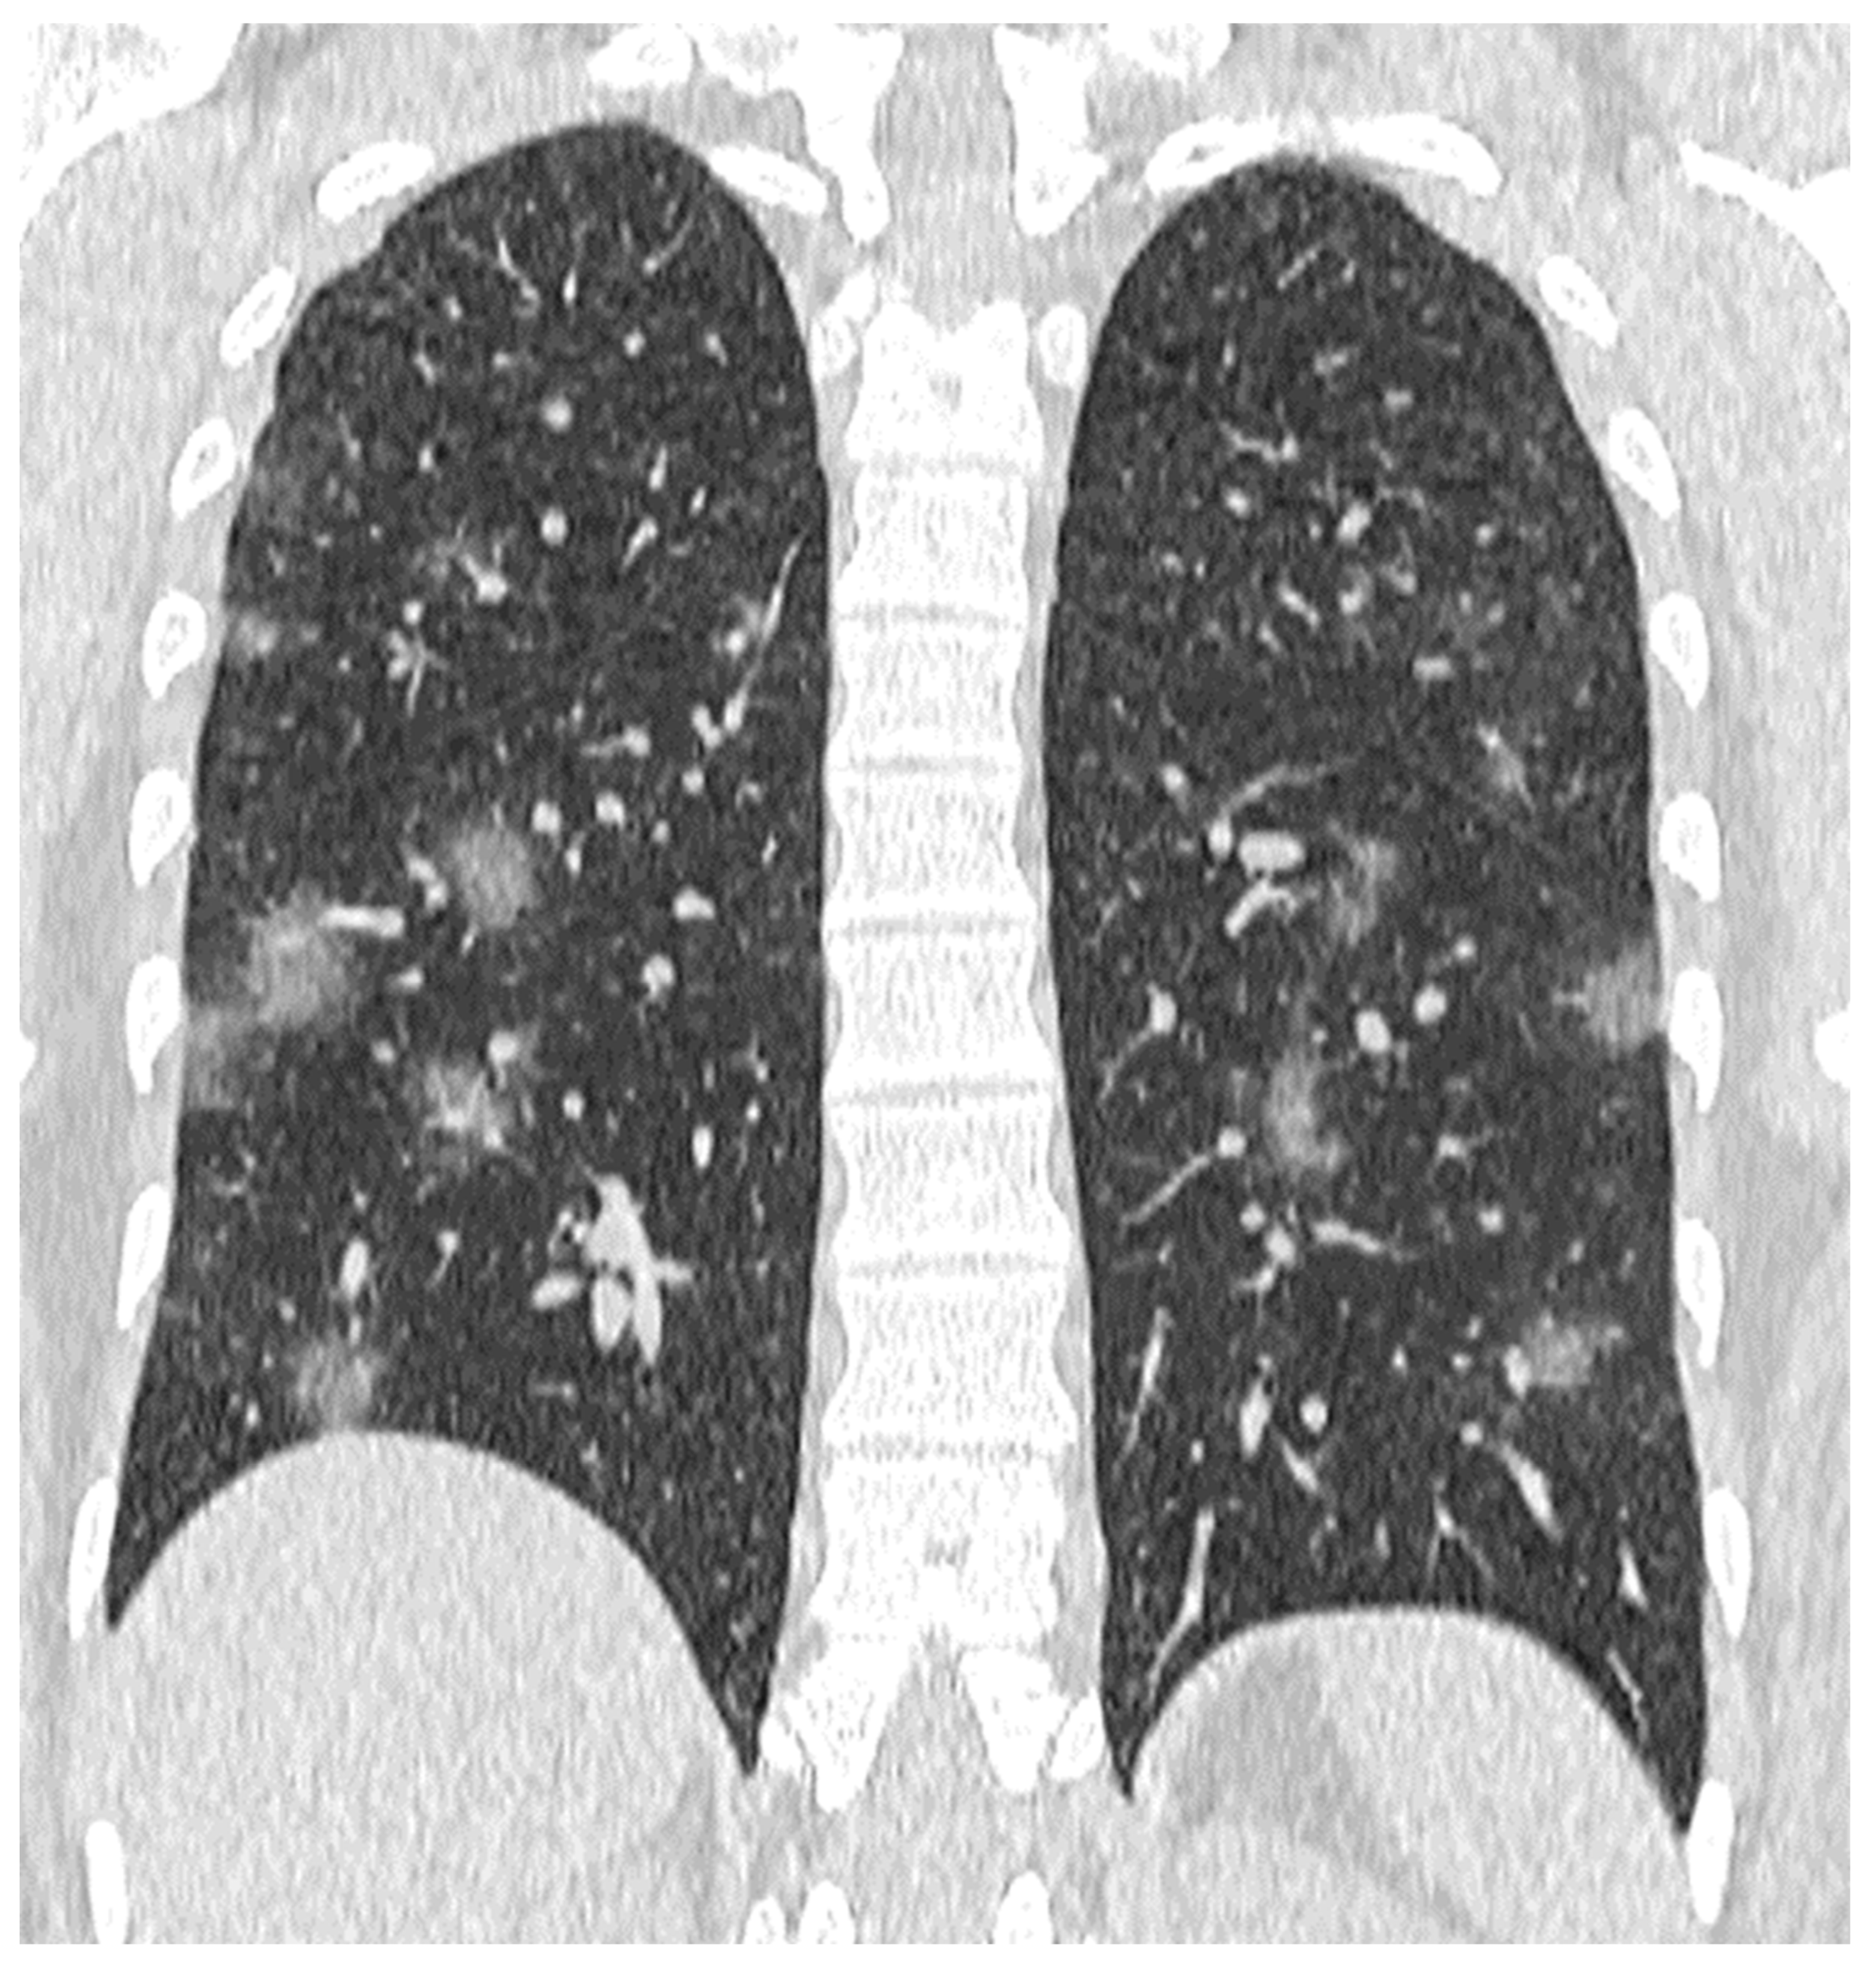

| GGO, N (%) | 446 (56) | 140 (36.1) | 306 (74.8) | <0.001 |

| Number of segments with GGO, median (SD) | 7.04 (3.7) | 3.69 (2.1) | 7.79 (3.57) | <0.001 |